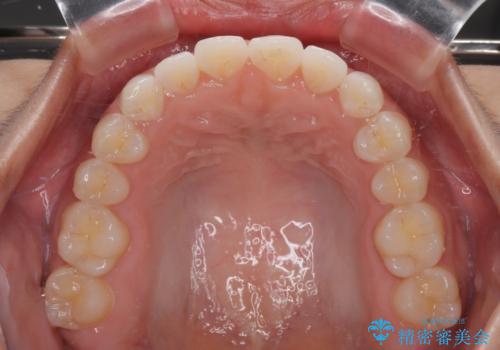

僅か半年強、あっという間に治療を終えることができました。

- 上下前歯のデコボコを気にして来院された患者様です。

ワイヤー矯正でもマウスピース矯正でも可能でしたが、短期間で、自身の手を煩わせることなく治療を行いたいとのことで、ワイヤー装置にて矯正治療を行うこととしました。